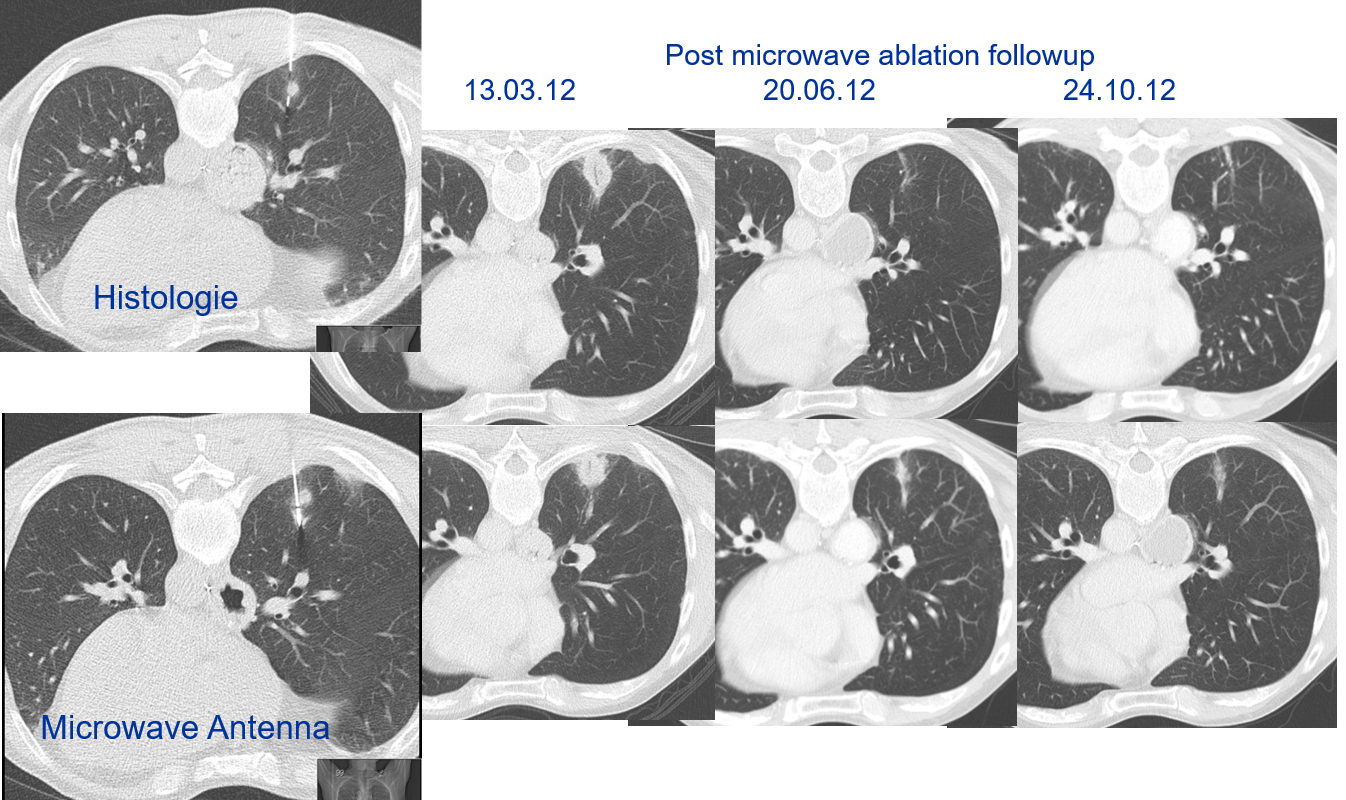

Doctors at National Taiwan University are successfully using microwave energy to minimally invasively treat tumors in the lung with higher local success rate of 84 percent compared to historical 67-78 percent.

The doctors apply microwave energy to destroy tumors located both centrally and peripherally within the lung using computer tomography (CT) image guidance. The tumors include colorectal cancer, lung adenocarcinoma, thymoma, uterine leiomyosarcoma and ampullary carcinoma in origination. Microwave energy applicators are introduced into the tumors in the lung percutaneously, a minimally invasive technique. A small hole is made through the skin near the tumor location and an applicator is inserted into the lung cavity and lung towards the tumor. Once the positioning of the antenna with respect to the tumor is verified with CT image guidance, microwave energy is applied to the antenna in contact with the tumor to destroy it. The procedures usually take an hour or two depending on the complexity of tumor location and shape to achieve good antenna positioning. The microwave energy application is controlled with direct temperature feedback from the ablation antenna during the procedure to ensure safety and efficacy. Temperature feedback control prevents overheating and runaway conditions and thereby provides the extra safety net for the patients and procedures.

AveCure® microwave ablation system is successfully treating tumors in the lung using a minimally invasive technique. The microwave ablation antenna is introduced through a percutaneous chest wall incision in the skin to access the tumor past the lung cavity and patient is left with a small hole in the skin which quickly heals with almost no scar after the procedure. AveCure® system utilizes a smart antenna in either probe or catheter format and microwave energy controller to select the correct size, temperature and timer settings appropriate for safe, effective and predictable treatment.